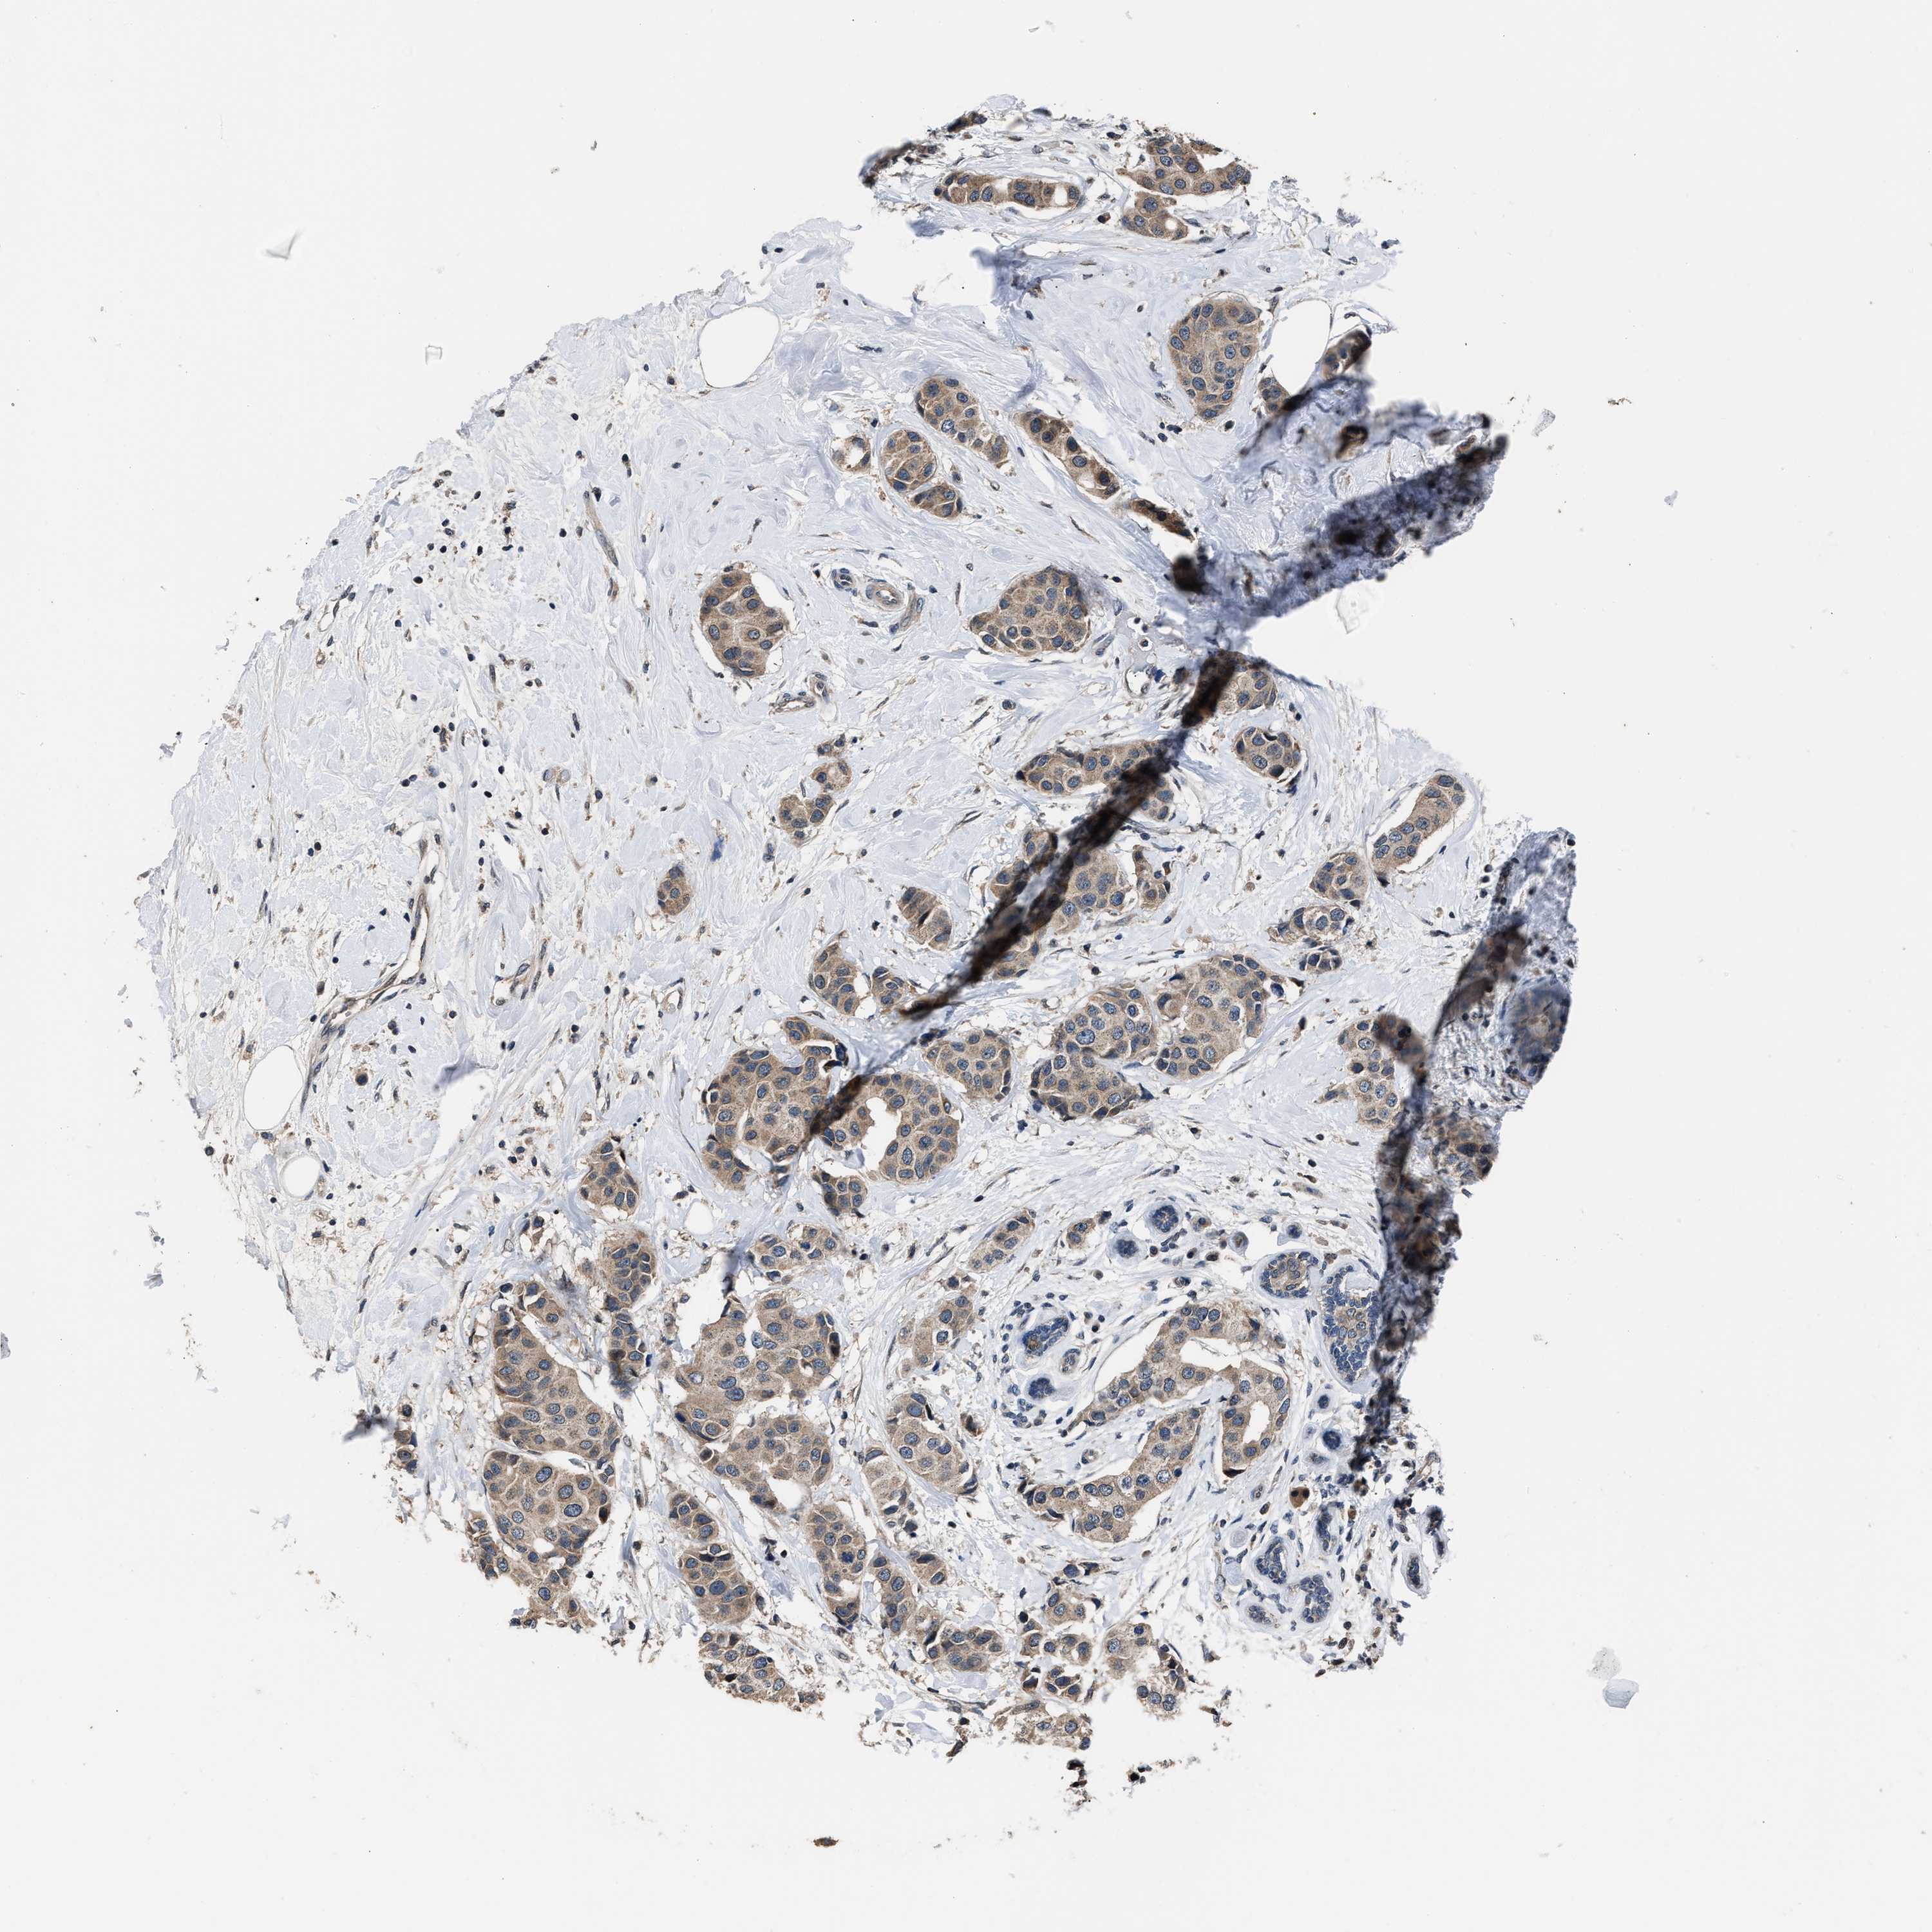

CANCER BREAST CANCER Show tissue menu

BRCA TCGA BRCA VALIDATION PROTEIN EXPRESSION